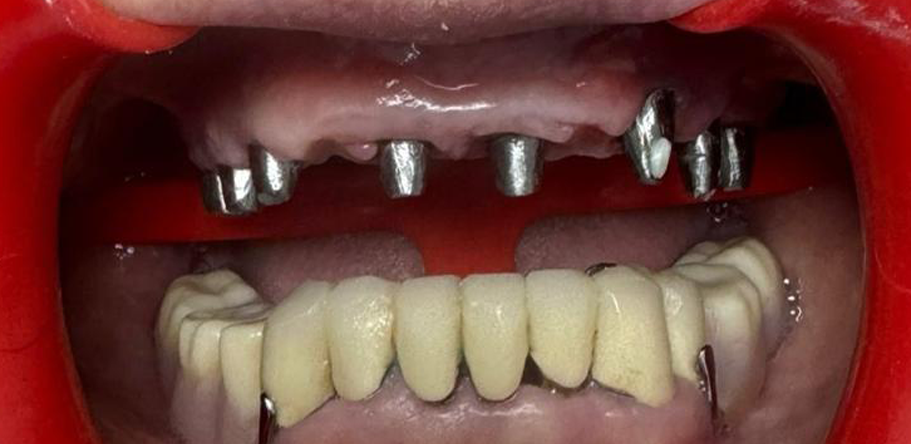

Antes

Después